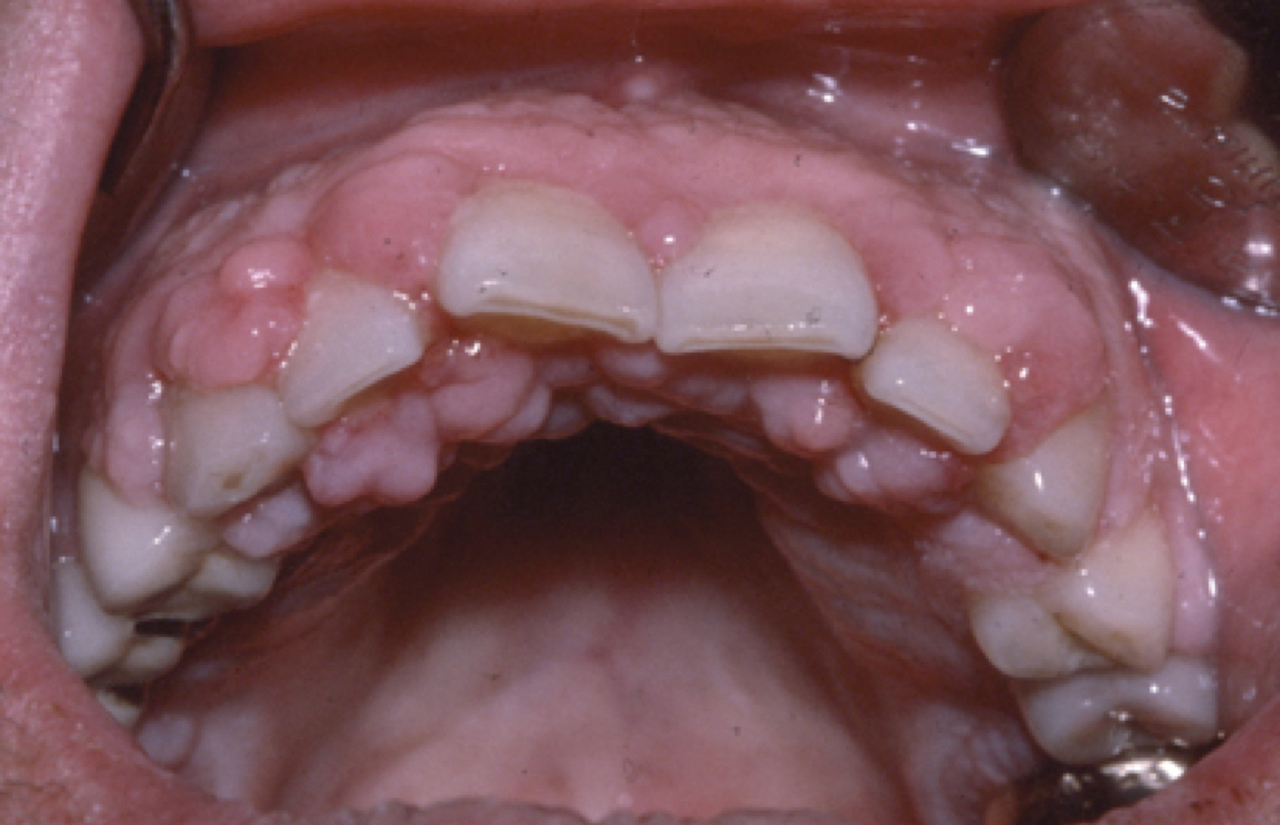

Les inhibiteurs calciques sont utilisés depuis une vingtaine d’années dans diverses indications cardiovasculaires, plus rarement dans l’athérosclérose, et d’autres pathologies.7 Une dizaine d’inhibiteurs calciques sont disponibles sur le marché. Trois d’entre eux peuvent induire des hypertrophies gingivales : la nifédipine (Procardia, Adalate), le diltiazem (Cardizem, etc.), le vérapamil (Isoptine, etc.) et la nicardipine (Loxen) [fig. 3 ]. L’hypertrophie gingivale observée n’a pas de particularité. Elle ne dépend pas de la dose et régresse spontanément à l’arrêt du médicament. L’association nifédipine-ciclosporine utilisée chez les transplantés rénaux n’entraîne pas d’augmentation de la fréquence de l’hypertrophie gingivale, mais une sévérité accrue.